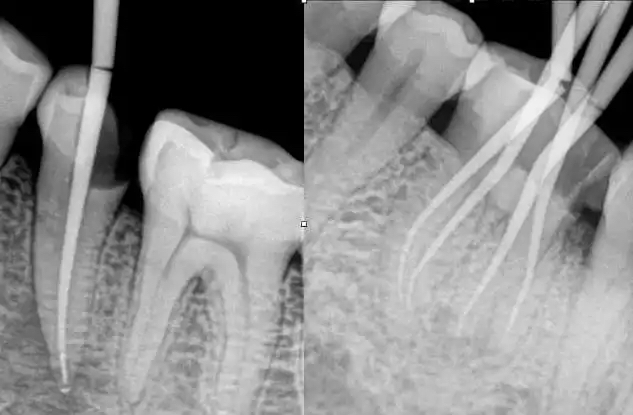

牙髓位于牙髓腔内,包含牙神经、血管和淋巴管等。通过血液供应系统获得营养,并通过成牙本质细胞及其突起向牙本质供应营养。牙齿出现损坏或者神经发炎,一般可以通过根管治疗的方式改善。根管治疗俗称“杀神经治疗”,是治疗牙髓病和根尖周病最常用、最有效的方法。主要是将牙神经杀死,将牙齿里面的牙髓组织抽取,然后通过药物填充保护牙齿。

磨牙承担的咬合力较大,发生劈裂的风险较高;前磨牙颈部缩窄,容易从牙颈部折断;前牙受侧向力,也容易折断;而牙齿劈裂或折裂后往往难以修复,常需进行牙齿拔除。因此,不论哪类牙齿接受根管治疗后,都建议进行牙冠保护,以避免不良情况发生。